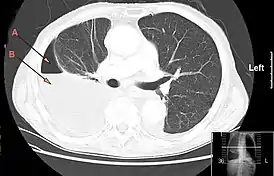

![]() Компьютерная томография, демонстрирующая массивный правосторонний гидропневмоторакс, обусловленный эмпиемой плевры. Стрелка A: газ, B: жидкость | |